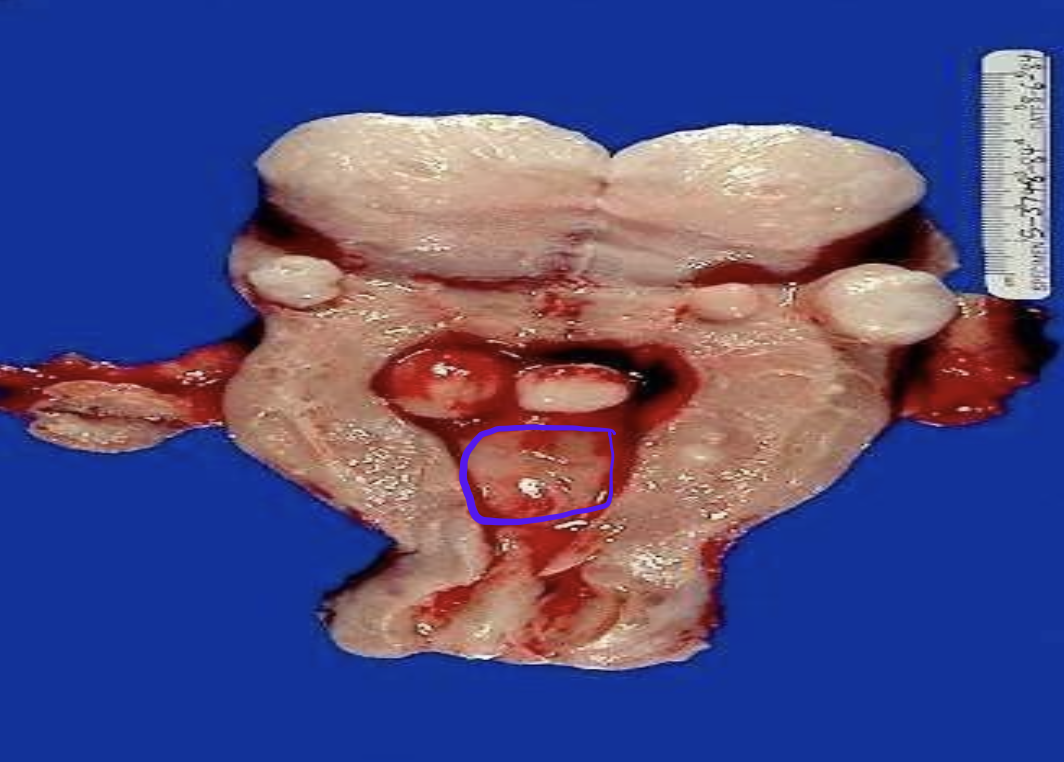

Identify the organ and the diagnosis in this format: diagnosis, organ

cystadenoma, ovary